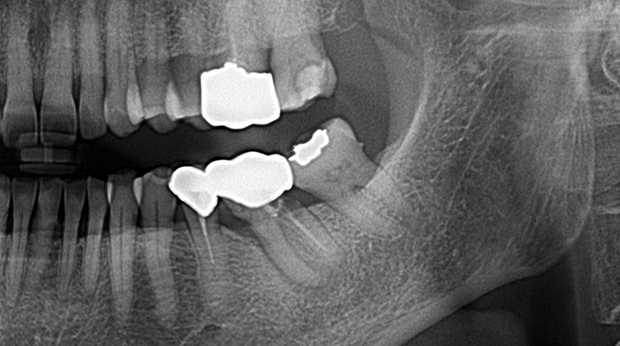

매복 사랑니 발치

의식하진정법(수면마취)/임플란트

임플란트와 사랑니 발치는 외과적 시술로 잇몸을 절개하는 외과적 시술은

짧으면 짧을 수록 시술 후 붓기와 통증이 최소화됩니다.

치과의사 경력 14년차 구강외과 전문의가 빠르고 안전하게, 아프지 않게 수술해 드립니다.